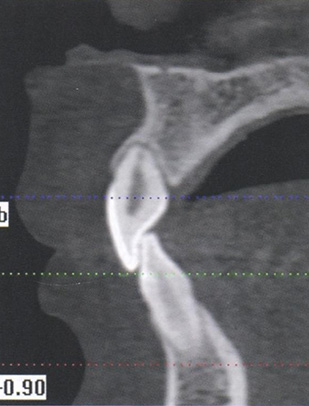

1) длину и форму корней зубов (рис. 76);

Оценка длины и формы корня зуба

Рис. 76. Оценка длины и формы корня зуба 2.1 на сагиттальных срезах компьютерных томограмм в окне мультипланарной реконструкции